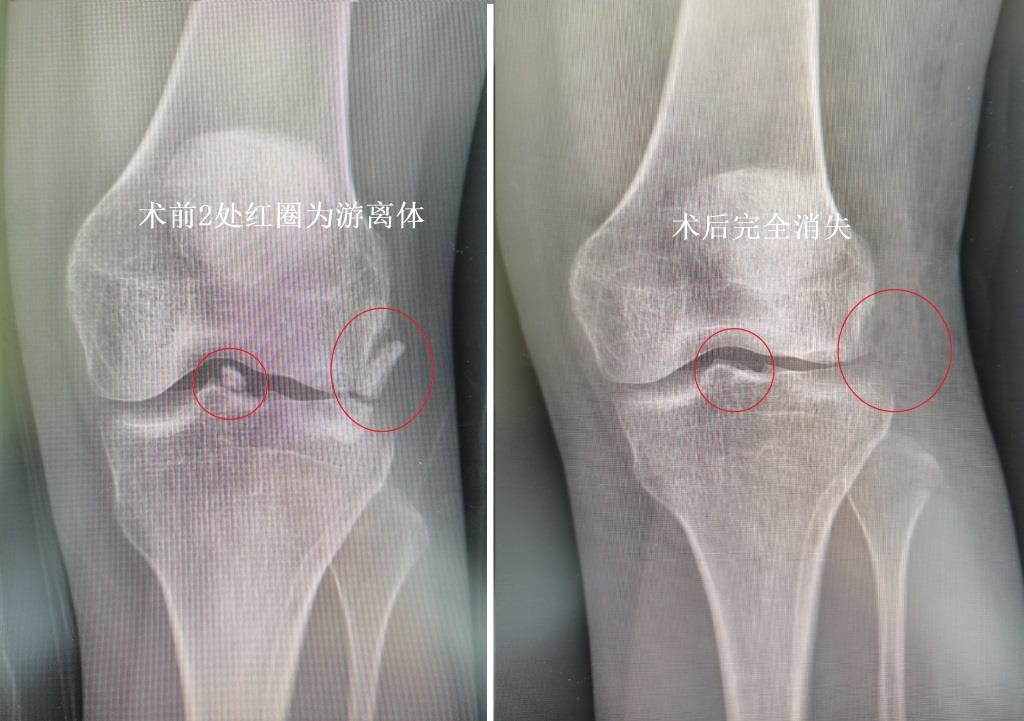

这些传统手术解决不了的难题,恰恰是关节镜手术的特长。膝关节镜是通过不到5毫米的皮肤切口将摄像头放入关节内,使用特殊的手术器材治疗关节内创伤的技术。经过周密的术前准备,给予该女士轻微的睡眠麻醉后,医生按照术前反复论证的手术方案,用时20分钟将2枚游离体全部取出。术后X线片可见游离体全部取出(如图1),术后第二天,该女士就可以完全蹲下(如图2),之前的疼痛感荡然无存!该女士及家人感激的同时更是觉得不可思议,困扰近20年的问题,仅仅20分钟通过小小的切口就彻底解决了!

图1. 术前膝关节X线可见有2处游离体,术后完全取出。